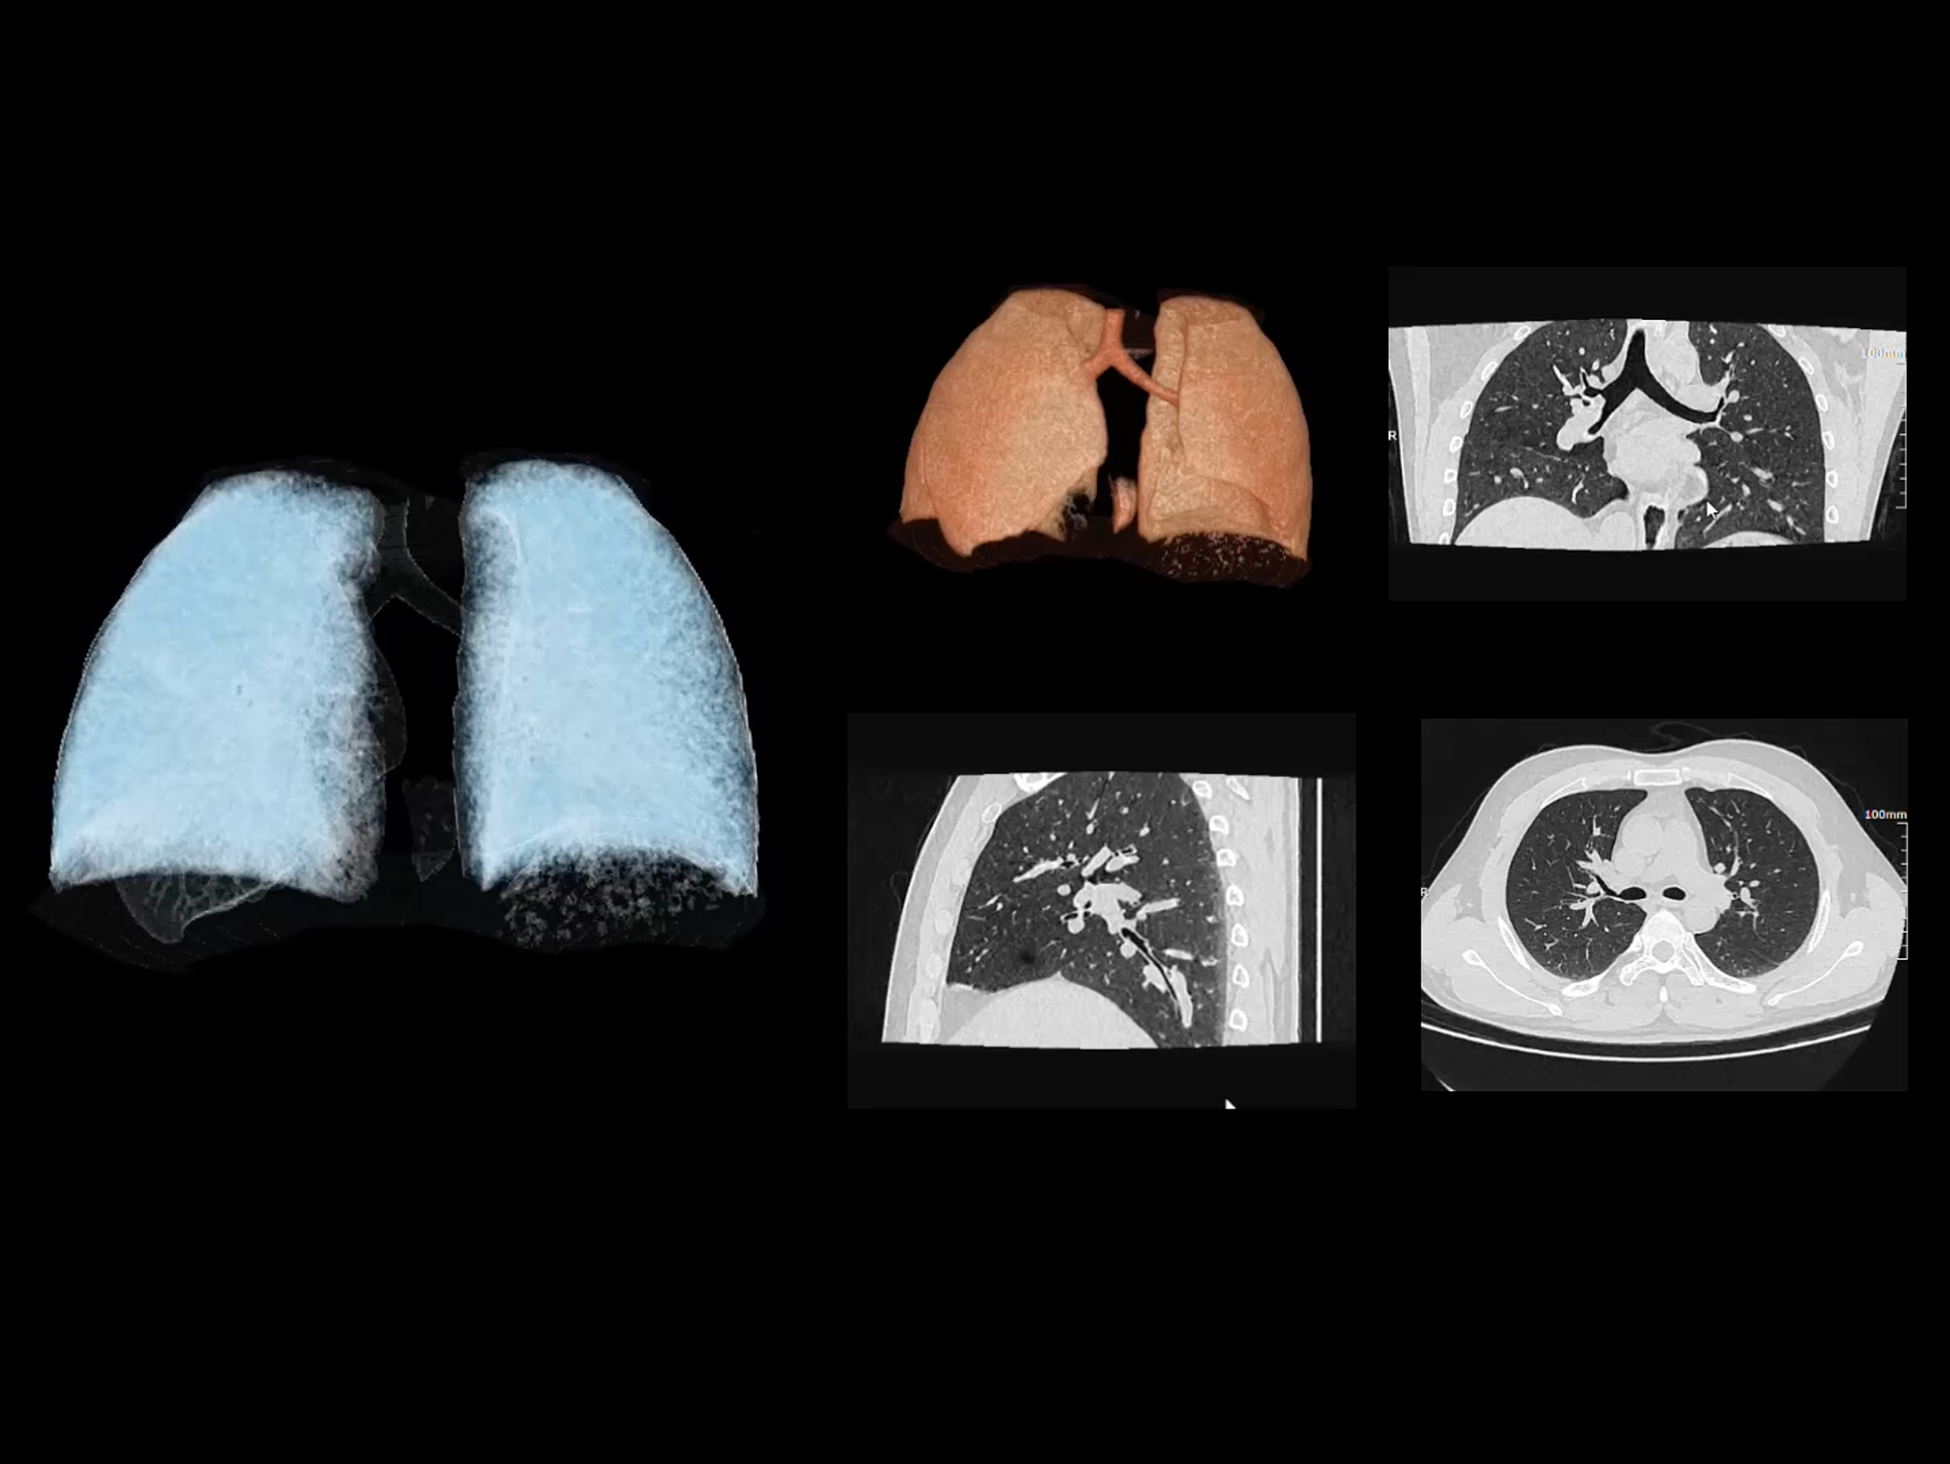

全域能谱

uCT SiriuX® 依托16cm超宽探测器与双源能谱技术,实现真正意义上的全身高清能谱成像。单次扫描同步获取灌注、能谱等多维定量参数,精准解析组织特性与病灶成分,为临床决策提供更深层次的诊断依据。

全身高清能谱成像

uCT SiriuX® 采用独有的双宽体探测器设计,实现470mm超大视野与全脏器容积覆盖的能谱成像,轻松应对不同体型患者和扫描部位应用需求。配合创新能谱重建影像链与精准双能数据配准,系统可有效抑制伪影、提升信噪比,在全脏器范围内提供高质量能谱图像,显著拓展临床精准诊断的广度与深度。